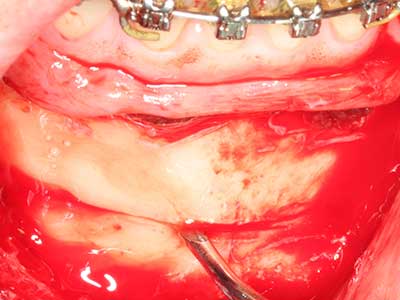

Abb. 22: Das mobile Segment kann präzise mit der dünnen Osteotomiesäge (W&H Piezomed) separiert werden.

Wie sich in der Vergangenheit gezeigt hat stellt prinzipiell jeder knochenchirurgische Eingriff eine mögliche Indikation für die Piezochirurgie dar. So lässt sich die Präparation des mobilen Segmentes bei der Distraktionsosteogenese (Abb. 23-25) und der Sandwichosteotomie mit speziellen Ansätzen bewerkstelligen, ohne die für den Erfolg beider Techniken essenzielle Blutversorgung des krestalen Anteils zu gefährden (Gonzalez-Garcia, Diniz-Freitas et al. 2008).